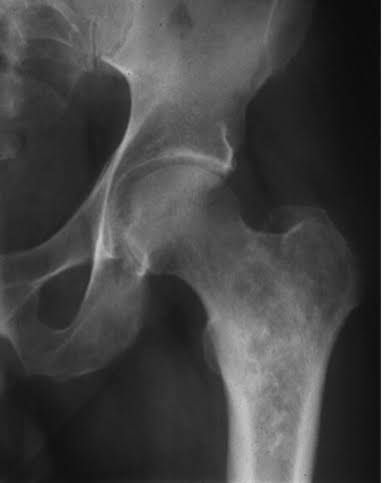

Chondrosarcoma

Chondrosarcoma is a rare type of cancer that usually begins in the bones, but can sometimes occur in the soft tissue near bones. Chondrosarcoma happens most often in the pelvis, hip and shoulder. More rarely, it can happen in the bones of the spine.